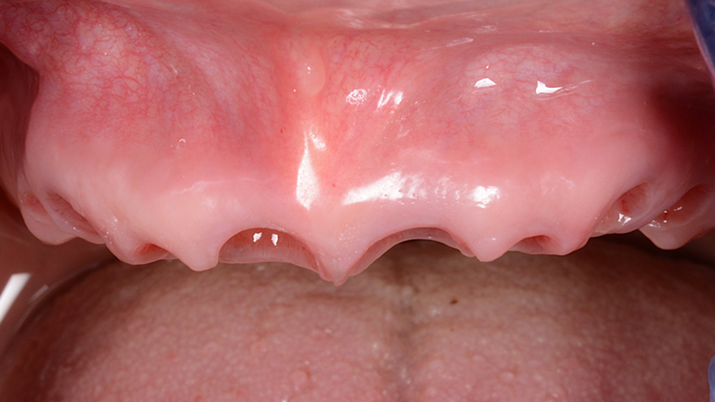

Clinical case: Extraction of all teeth in upper maxilla,

immediate implant placement, & provisionalization

- Courtesy of Dr. Iulian Filipov, Romania -

Keywords

AnyRidge, immediate placement, immediate provisionalization, maxillary fully edentulous case, initial stability, edentulous, Dr. Iulian Filipov, R2GATE, MEGA ISQ

Products:

AnyRidge implant system, Mega ISQ, R2GATE

“AnyRidge ensures long-term biological stability

& functionality even in

full-mouth rehabilitation case. ”